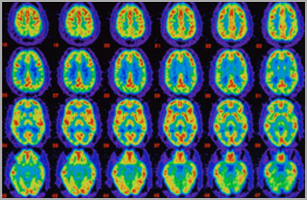

- Viaggio nel cervello

È in corso una ricerca a livello mondiale per trovare nuovi metodi di trattamento, prevenzione, e, in ultima analisi, una cura per il morbo di Alzheimer e le altre demenze progressive. Oggi, i trattamenti si rivolgono solamente ai sintomi del morbo di Alzheimer; tuttavia gli scienziati continuano a studiare modi per fermare o rallentare l’avanzamento della malattia, identificare i fattori di rischio e migliorare la capacità di diagnosticare il morbo di Alzheimer in una fase precoce del processo della malattia.